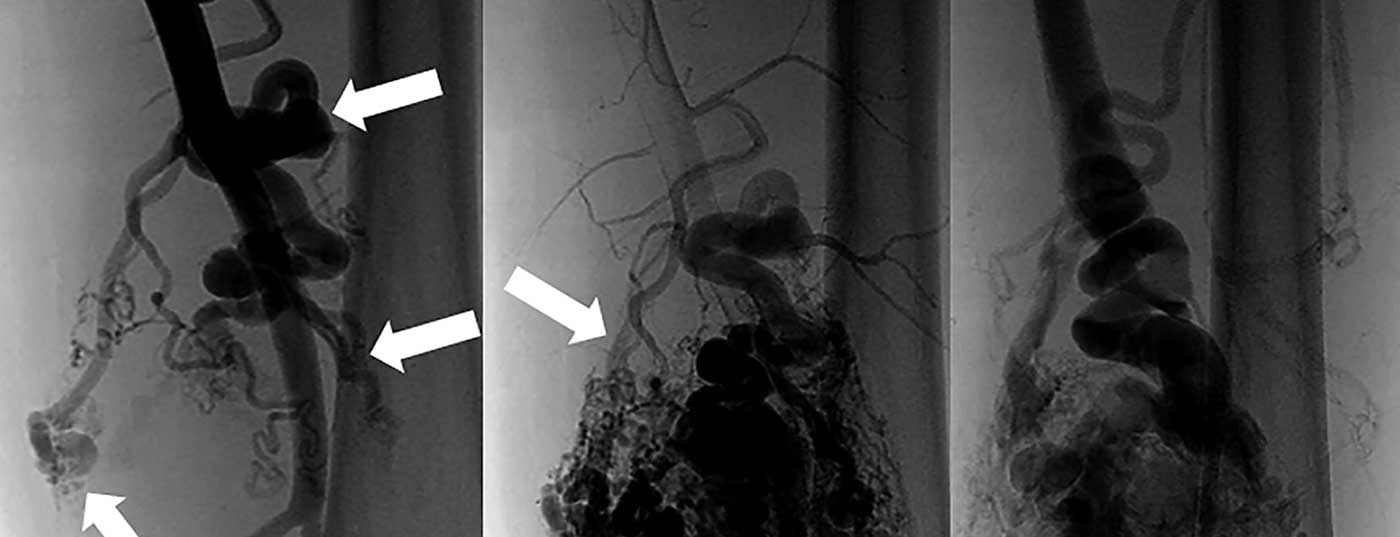

Arteriovenöse Malformationen (AVM) bestehen aus kongenitalen multiplen direkten Verbindungen zwischen Arterien und Venen. Ein Wachstum mit hieraus resultierenden möglichen Komplikationen wie Blutungen, Schmerz und Ulzerationen ist zu fast 100% zu erwarten. Die notwendige multidisziplinäre Behandlung von Patienten mit arteriovenösen Malformationen sollte an hierfür spezialisierten Zentren durchgeführt werden. Arteriovenöse Missbildungen sind meist chronische Erkrankungen, da sie selten kurativ behandelbar sind. Nur falls eine vollständige chirurgische Entfernung möglich ist, kann die AVM kurativ behandelt werden. Hierfür ist eine frühzeitige korrekte Diagnosestellung unerlässlich. Die Behandlung von chirurgisch nicht vollständig resezierbaren AVM ist komplex und bedarf mehrerer Eingriffe, wobei das Therapieziel primär die Symptomkontrolle ist. Der interventionelle Verschluss der venösen Anteile der AVM stellt eine sehr gute Therapieoption dar.